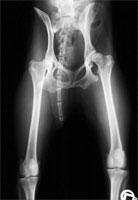

In den Fällen einer extremen Lockerheit der Hüftgelenke kann die Verbesserung der Abdeckung durch den dorsalen Rand des Acetabulums zunächst enttäuschend erscheinen (Abb 14 a, 14 b und 14 c) und ein gewisser Grad an Subluxation noch erkennbar sein. Diese Befunde verschwinden jedoch innerhalb weniger Wochen unter Belastung des Gelenkes, ohne besondere Maßnahmen zu erfordern.

HD vollständige Luxation

Abbildung 14 a: Extreme Lockerheit und Luxation der Articulatio coxae

schwere HD mit Luxation nach DBO

Abbildung 14 b: Bei gestreckten Hüftgelenken erscheint die Hüfte gut stabilisiert.

Abbildung 14 c: In der Beugestellung zeigt sich eine enttäuschende Lockerheit